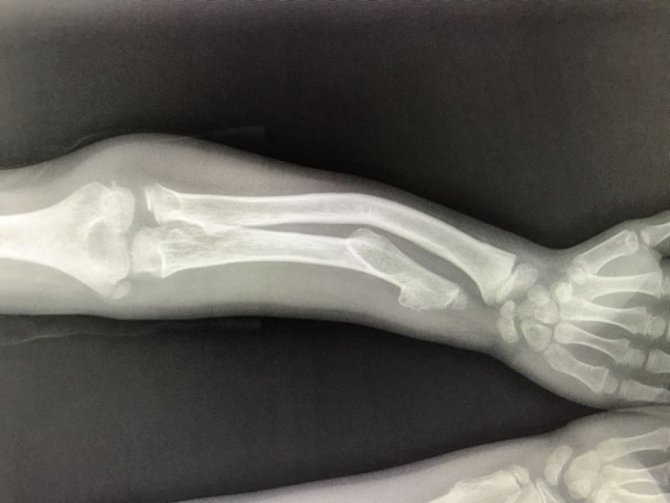

Kolda meydana gelen şişlikler tümör kaynaklı da olabilir. Bu durumda oluşan tümörün malign yada benign kaynaklı olup olmadığı tespit edilmeli ve buna uygun tedavi uygulanmalıdır. Kansere neden olan tümör 2 inci kaburganın üst kısmına boyuna ve omuza yakın bölgede yapılanıyor. Epilepsi sara nöbeti de görülebilir.

Kolda tümör oluşmasına neden olan en önemli unsur aşırı ışına maruz kalmaktır. Travmaya bağlı olmayanlar ise tümör iltihap omurda dejenerasyonu ve romatizma sayılabilir. Tümör kemikte ortaya çıkabilir ya da meme akciğer böbrek ve prostat kanserlerinin metastazları olarak kemiklerde görülür. Genel anlamda kolda sivilceye benzeyen şişlik genel anlamda tümör enfeksiyon ya da travma gibi durumlardan dolayı herhangi bir yerinden kaynaklanmaktadır.